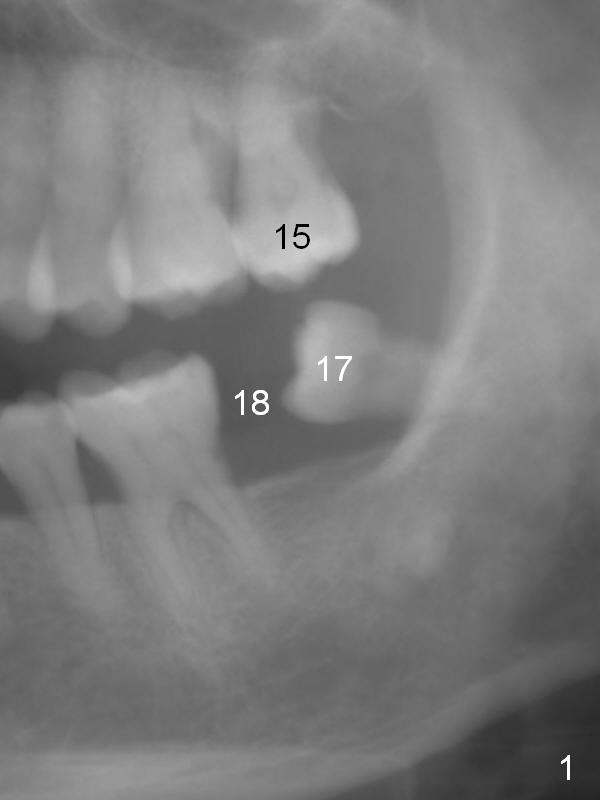

A 53-year-old lady has a small statue.  The tooth #18 was extracted due to #17 impaction (Fig.1).  To prevent further supraeruption of #15, an implant is to be placed at the site of #18 (Fig.2).  After use of a 4 mm implant spacer and starter and 8 mm pilot drills, insert a short parallel pin for occlusion check and a calibrated one for X-ray.  A relatively small and short implant will be sufficient for function.  Scaling & root planing and #17 extraction have been finished.